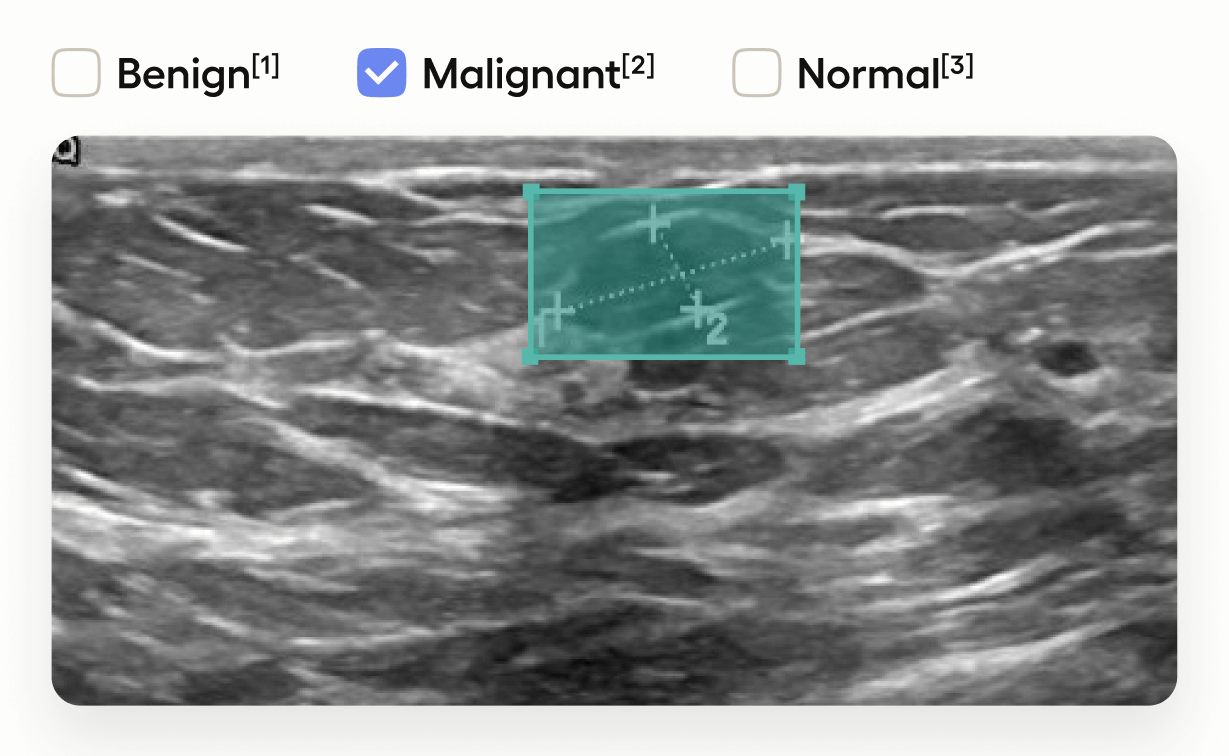

This template interface allows annotators to:

• Draw bounding boxes around areas identified as tumors in the image using the โ€œTumorโ€ label.

• Classify the entire image by selecting one of โ€œBenignโ€, โ€œMalignantโ€, or โ€œNormalโ€.

This setup is useful in medical imaging tasks where you need to localize tumors and also provide an overall assessment of the image.

This adds image-level classification choices.

• The <Choices> tag provides a set of options for annotators to select.

• toName="image" applies these choices to the entire image.

• Annotators can classify the image as โ€œBenignโ€, โ€œMalignantโ€, or โ€œNormalโ€.